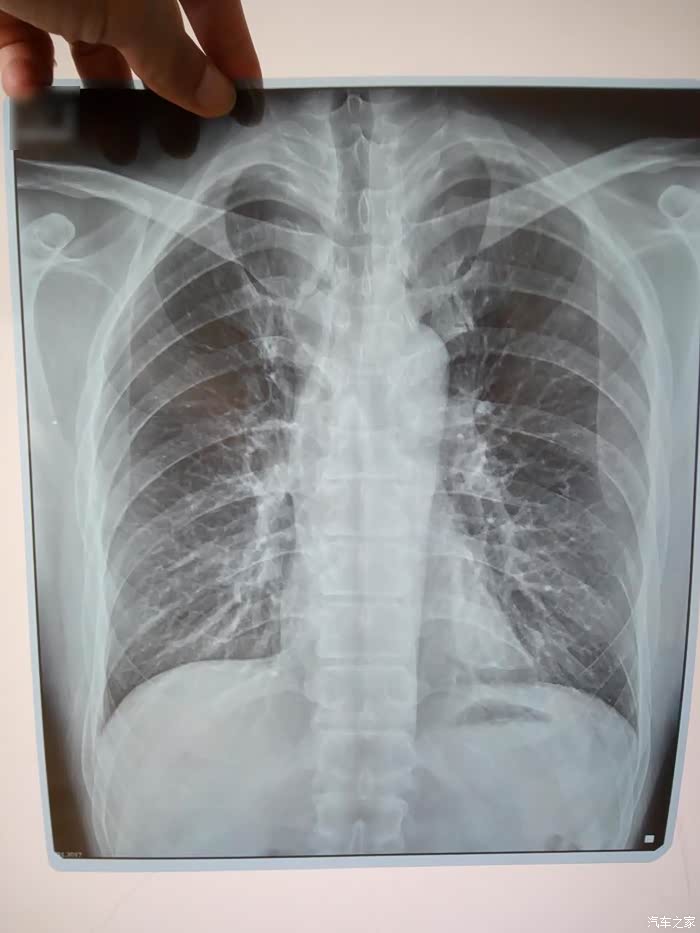

胸片,可见纤维化的印迹

昨天去因为胸痛去做了X光,没有发现肿瘤和异常,但是,【肺部轻微纤维化】!这也是开小五以来,一直感受到异味导致胸闷胸痛的原因!我很庆幸,没有什么其他的东西,但是也很担心,纤维化无法逆转。建议车友们购买防毒面具,并且尽一切可能做好通风工作。。。我已经买了皮套来更换车里的座椅,希望能有所好转。。。。上天保佑。。。